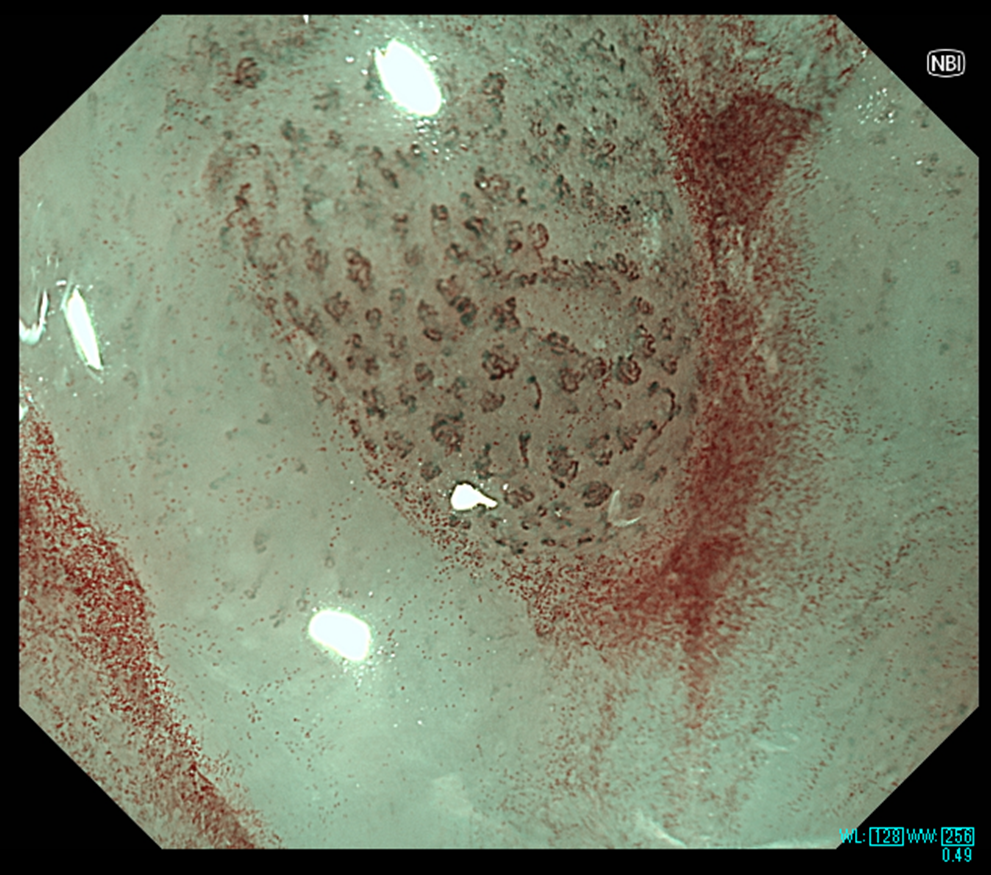

(2組)食道表在癌の拡大観察時の画像

NBI(左)よりもNBI+TXI(右)ではIPCLが強調されており、より明瞭に観察される。